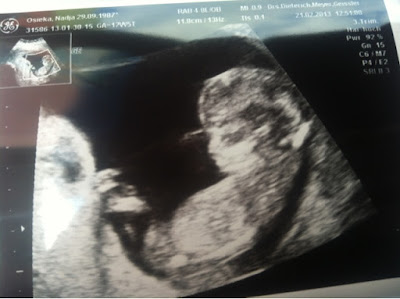

Krümel-TV

Ich weiß nicht wie ich es nun 4 Wochen aushalten soll ohne meinen Krümel zu sehen.

Es war einfach wieder total toll, ich hatte wie immer etwas Angst vor dem Termin aber die ist sofort weg wenn ich höre, dass alles OK ist wenn ich mein Krümel sehe und sein Herz schlägt. Was es wird naja das konnte man raten aber Sie wollte nichts sagen noch zu unsicher :) Meine Mama war dabei und die war auch ganz gerührt. Beim 3D war es echt lustig, Krümelchen hat erst wild Party gemacht und dann Beine und Arme verschränkt und runter geschaut wie ein kleiner Buddah sass der Krümel in seiner Höhle. Ich liebe Ihn so sehr so sehr so sehr.....